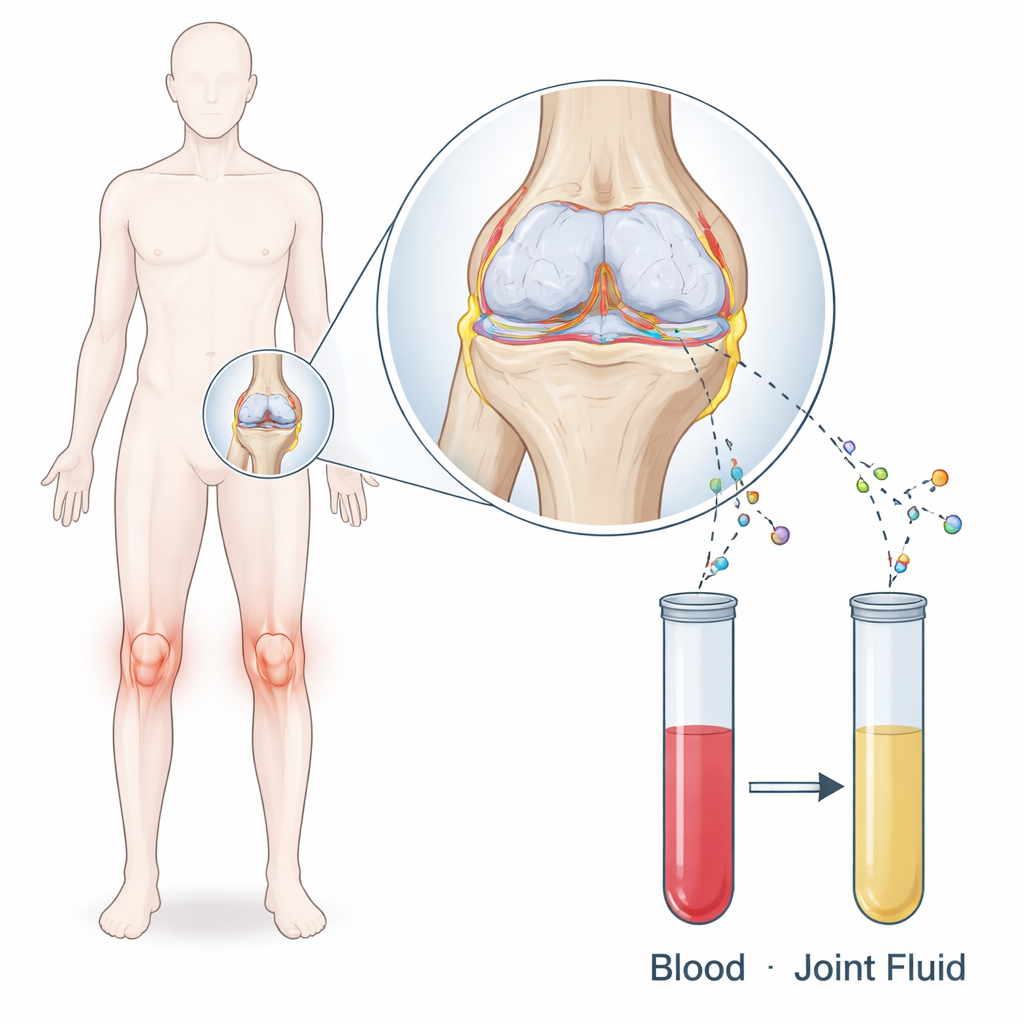

L’osteoartrite è più della semplice “usura”. Man mano che la cartilagine liscia che ammortizza le ossa si degrada, l’ambiente articolare si riempie di messaggeri chimici rilasciati dalle cellule danneggiate e dai tessuti circostanti. I ricercatori si sono concentrati su tre di questi messaggeri: MMP‑1, un enzima che contribuisce alla degradazione della cartilagine; IL‑8, un segnale che richiama cellule infiammatorie; e IL‑18, un altro segnale infiammatorio noto per influenzare il rimodellamento osseo. Volevano sapere se i livelli di queste sostanze nel sangue e nel denso liquido articolare che bagna il ginocchio fossero legati alla dimensione degli osteofiti, le creste ossee che si formano al margine delle articolazioni artrosiche.

Lo studio ha arruolato 44 pazienti, per lo più donne anziane, tutte con gonartrosi in fase terminale così grave da essere programmate per una sostituzione totale del ginocchio. Il giorno dell’intervento il team ha prelevato sangue e raccolto direttamente il liquido articolare dal ginocchio. Con test di laboratorio sensibili hanno misurato i livelli di MMP‑1, IL‑8 e IL‑18 in entrambi i fluidi. Per valutare la dimensione degli speroni ossei hanno analizzato le radiografie in stazione eretta di ciascun ginocchio. Due chirurghi esperti hanno tracciato l’area delle escrescenze ossee sul lato interno del femore e della tibia usando uno strumento digitale “a mano libera”. Ripetere le misurazioni ha mostrato che questo metodo era affidabile, con piccole differenze tra i lettori e nel tempo.